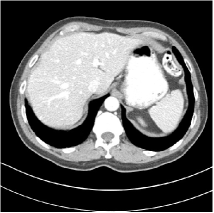

Refer to caption WavResNet [11]Refer to caption WavResNet [11]Refer to caption WavResNet [11]Refer to caption Momentum-Net (SimpleCNN)Refer to caption Momentum-Net (SimpleCNN)Refer to caption Momentum-Net (SimpleCNN)Refer to caption Momentum-Net (SimpleCNN-RSN)Refer to caption Momentum-Net (SimpleCNN-RSN)Refer to caption Momentum-Net (SimpleCNN-RSN)Refer to caption Momentum-Net (Dn-RSN)Refer to caption Momentum-Net (Dn-RSN)Refer to caption Momentum-Net (Dn-RSN)Refer to caption ReferenceRefer to caption ReferenceRefer to caption Reference

Fig. 3: Three examples (from top to bottom) of the reconstructed testing images using Momentum-Net with SimpleCNN (the second column), with SimpleCNN-RSN (the third column), and with Dn-RSN (the fourth column). The compared WavResNet denoised images are shown in the first column, and the reference images are in the fifth column. See their FBP images in Fig. 4.

Fig. 2 shows that the proposed Momentum-Net with SimpleCNN decreases RMSE dramatically in the first 30 layers, and tends to converge in 50 layers. The Momentum-Net reduces the mean RMSE value by 4.5 HU and gives smaller standard deviations in RMSE, compared to WavResNet, as reported in Table 1. This implies that the proposed Momentum-Net with SimpleCNN can improve both the accuracy and stability of low-dose CT image reconstruction than a state-of-the-art image denoising deep NN, WavResNet. The proposed Momentum-Net with SimpleCNN better removes noise and streak artifacts than WavResNet. It also provides clearer reconstructions of some details; see, in Fig. 3, the boundaries shown in the zoomed region at the top-right corner in the first example, the arrow pointed structures in zoomed areas of the second example, and the arrow pointed tissues in the left zoomed region in the third example.

3.3 Momentum-Nets involving RSN-based training